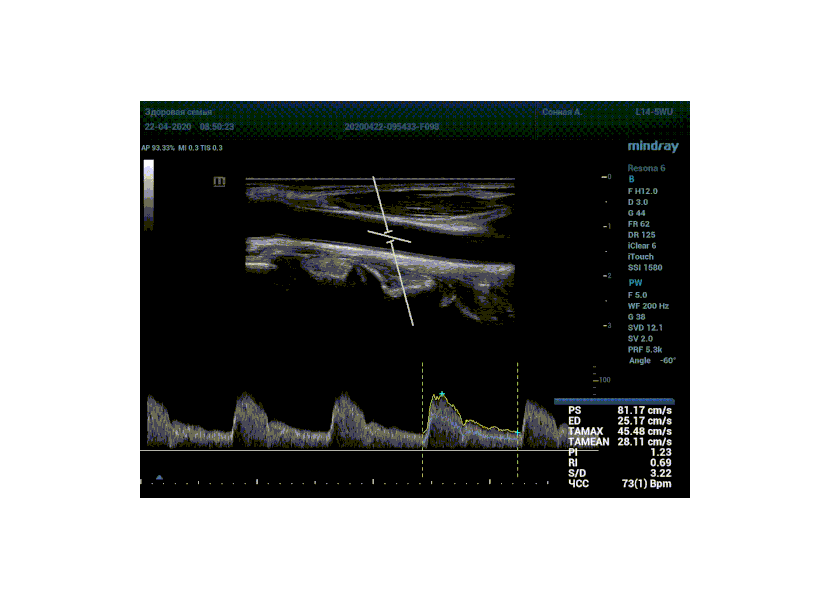

Особо ценна данная функция при исследовании тяжести стеноза. Доктор проводит санирование методом «утюжка» или же проводит «прогулку по стенозу» смещая зону опроса импульсно-волнового допплера. Таким образом проводит поиск максимальную скорость в струе элайзинга. Ранее максимальная скорость определялась на глазок, с дальнейшим измерением, либо серией измерений вручную. Теперь прибор сделает всё сам, без отрыва от движения, автоматически измеряя её в режиме реального времени.

Какие показатели выдает автоматический расчет? Доктор может настроить расчет под себя, под свои собственные желания. Стандартно выставлены показатели пиковой (PS) и конечной диастолической скорости (ED), TAMAX, TAMEAN, Pi, Ri, S/D соотношение и ЧСС. Можно дополнить из списка показателей: MD, PPG, Объемный поток, DT, AT, MPG, MMPG, VTI, D/S соотношение. Прибор подстраивается под Вас, а не вы под прибор.